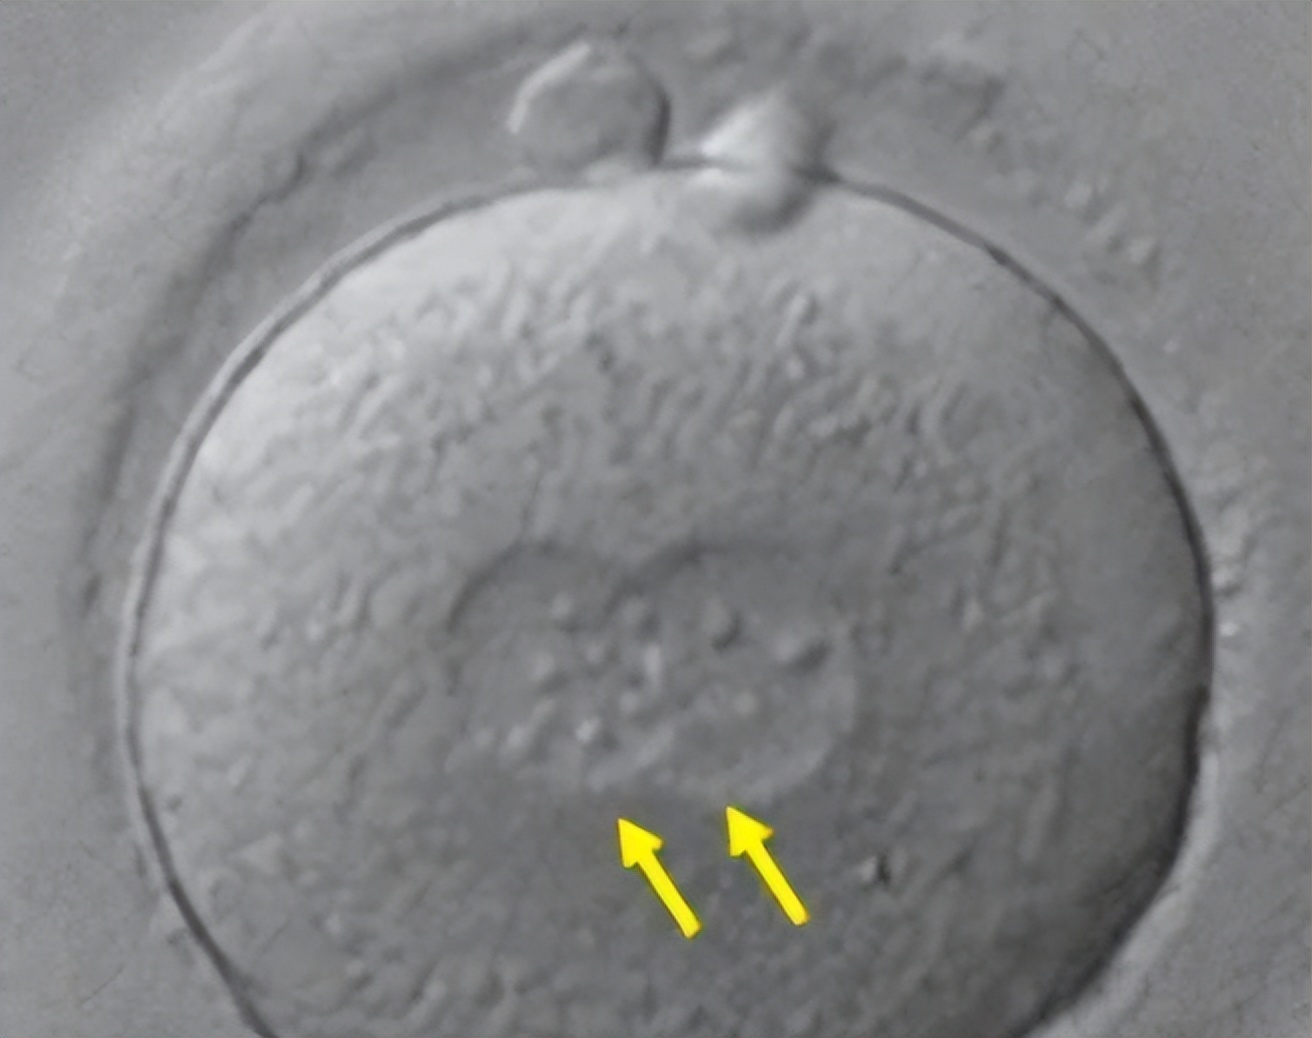

二、非线段模式——“圆形”

这种模式常见于CMN、EDM和PPV,很少见于NF1中巨大的先天性café—au—lait斑。

这种图案的特征可以概括为圆形边缘定义,形成粗糙的圆形或卵形。

为了演示这种模式,我们将重点关注与单个黑素细胞前体场相对应的一系列皮肤区域,使用CMN病例作为模型确定每个区域的最大范围。

总的来说,在这个新群体中,我们估计大约有12-13个奠基黑素细胞前体。

然而,根据将这些领域映射到成人身体地图上,这两个领域之间有 相当大的重叠。

在这个群体中,也有一些缺失的区域,特别是眼睛周围、嘴巴周围、在一定程度上在手掌和鞋底,以及指尖/甲床。